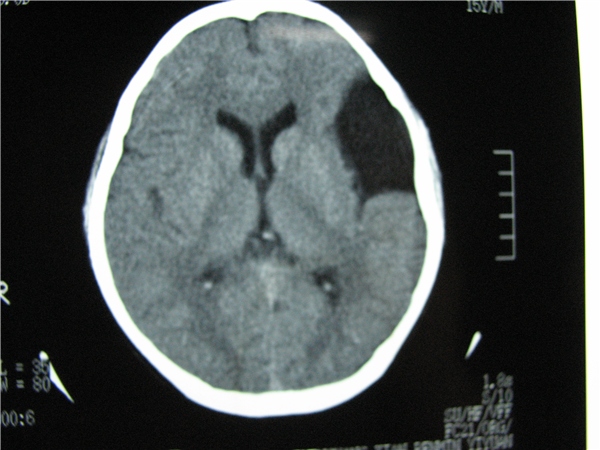

标题: CT20748:M 15Y 头痛,以前有外伤史请老师看看除了囊肿还有别 [打印本页]

标题: CT20748:M 15Y 头痛,以前有外伤史请老师看看除了囊肿还有别

m 15y 头痛,以前有外伤史请老师看看除了囊肿还有别的吗?

蛛网膜囊肿。眼拙,看不出别的,倒是看到了双侧大脑中动脉影,类似“致密动脉征”。

双侧侧裂池和纵裂池近前颅窝蛛网膜囊肿。

不能除外脑穿通畸形

无明显占位及负占位效应,考虑软化灶并脑室穿通畸形囊肿、局限性脑萎缩

蛛网膜囊肿,不能除外脑穿通畸形,支持。